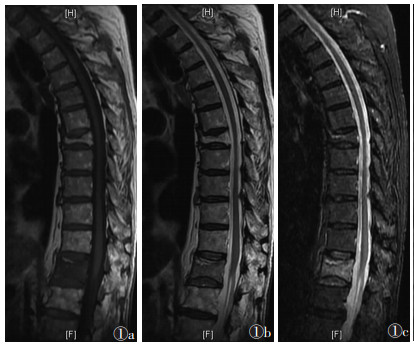

168节椎体中,轻度骨髓水肿32节,中度70节,重度66节。随时间推移,骨髓水肿信号强度逐渐由均匀向非均匀转变,信号范围逐渐减小,边界逐渐清晰;轻度骨髓水肿发生率由8.4%升至50.0%,重度由51.8%降至8.3%,差异均有统计学意义(均P<0.050.05)(表 3)。①Ⅰ期:骨髓水肿比例迅速上升,达到峰值。T1WI、T2WI信号均匀分布,T1WI呈低信号,T2WI和STIR呈高信号,扩散至正常骨髓,呈弥漫性、均匀性、边界不清的形态分布(图 1)。②Ⅱ期:信号分布变得不均匀,水肿范围逐渐受限,并出现点、片状T1WI低信号,T2WI和STIR高信号(图 2)。③Ⅲ期:骨髓水肿较前一期下降,水肿范围局限于骨折区,信号混杂;部分椎体T1WI呈等、低信号,T2WI及STIR呈低、等、高信号(图 3)。④Ⅳ期:骨髓水肿百分比降至最低。T1WI骨折区可见低信号区,边界清晰。T2WI和STIR信号与相邻正常椎体相同(图 4)。

| 图 1 男,85岁,Ⅰ期骨质疏松性椎体压缩骨折(OVCFs)。MRI示骨折位于T12,T1WI(图 1a)呈均匀低信号,T2WI(图 1b)和STIR(图 1c)呈均匀高信号。上终板下方线性透亮影表示断裂线,T12呈双凹畸形 |